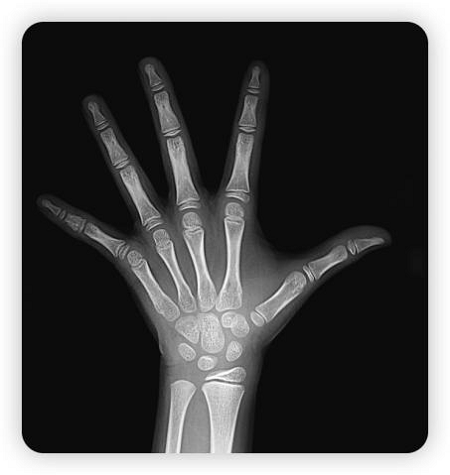

骨骺线尚未闭合状态